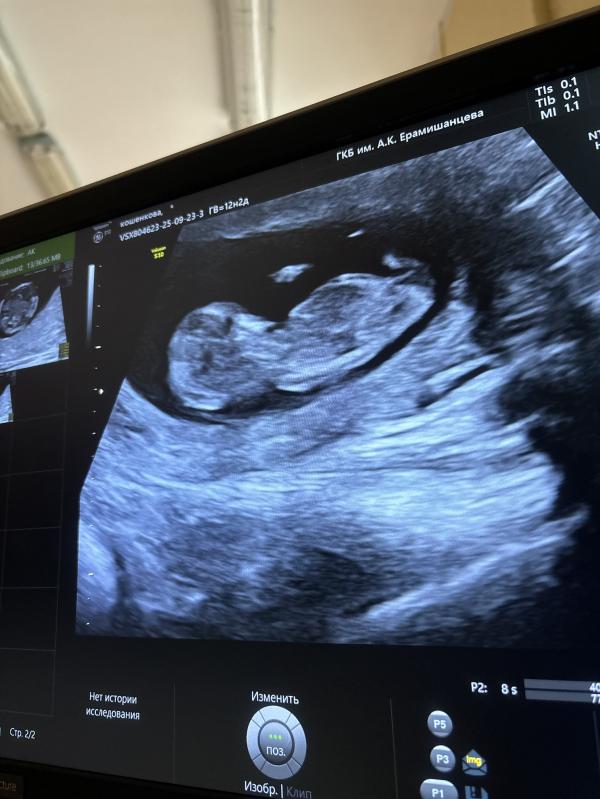

Мальчик или девочка )? Как думаете на снимке узи мальчик или девочка ? То что торчит это пуповина или половой бугорок 🙈? Погадаем ) 😅срок 12.1

Хотелось бы вам пожелать девочку, но кажется мальчик.. Ждите 20 неделю или анализ крови на y хромосому